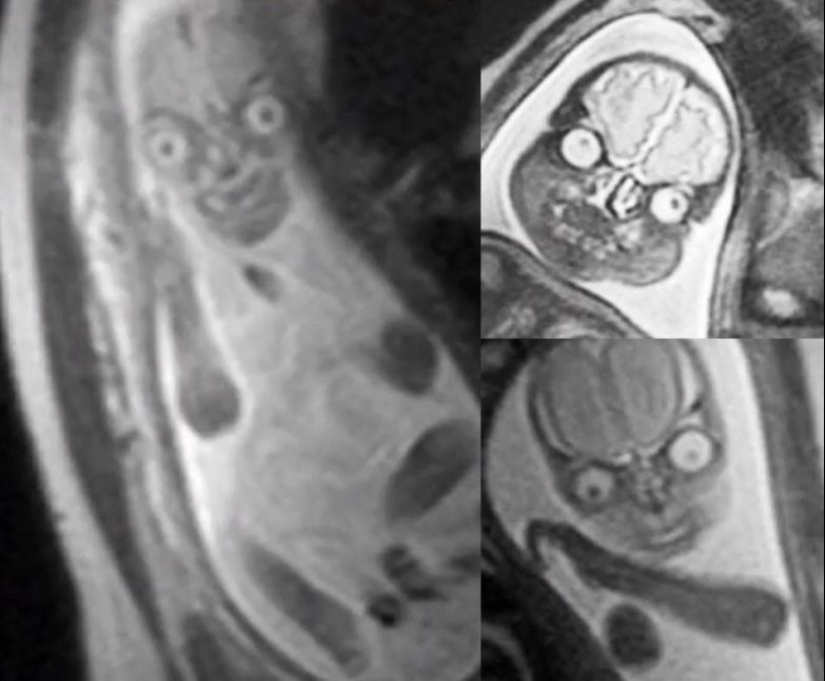

Resonancia magnética del feto en el estómago de las mujeres embarazadas